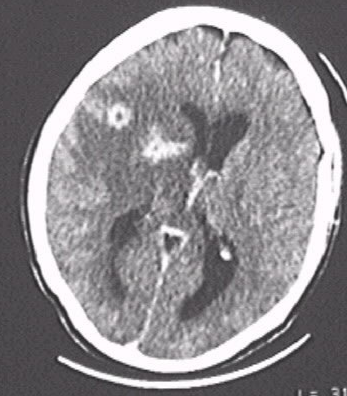

TC de crânio c/ lesão sugestiva de Neurotoxoplasmose.